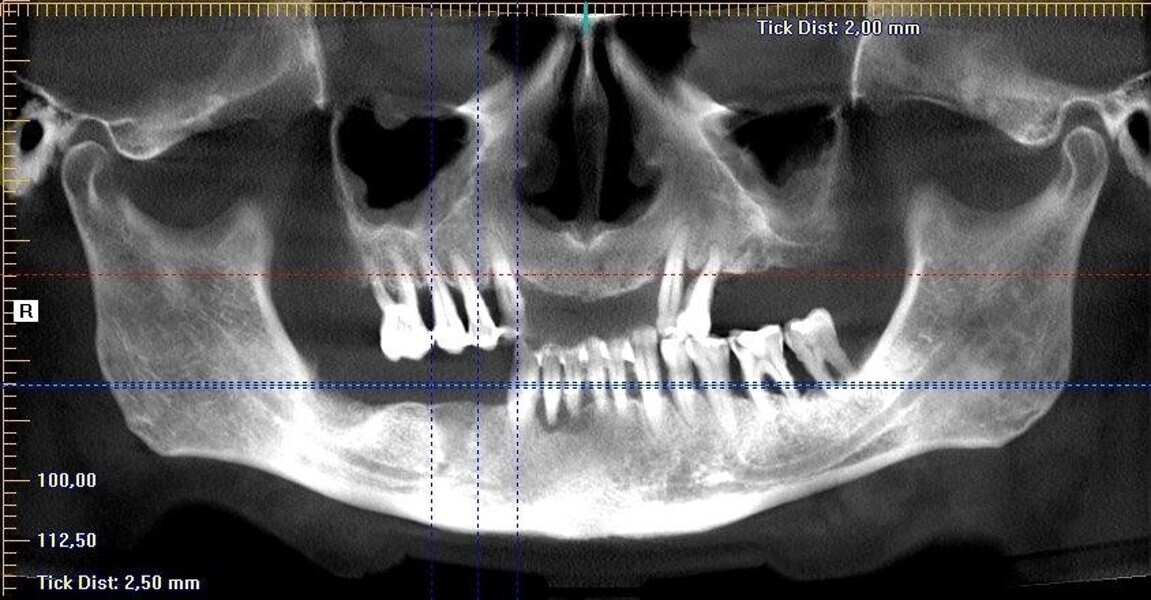

Implantacja z wykorzystaniem szablonu nawigacyjnego 3D